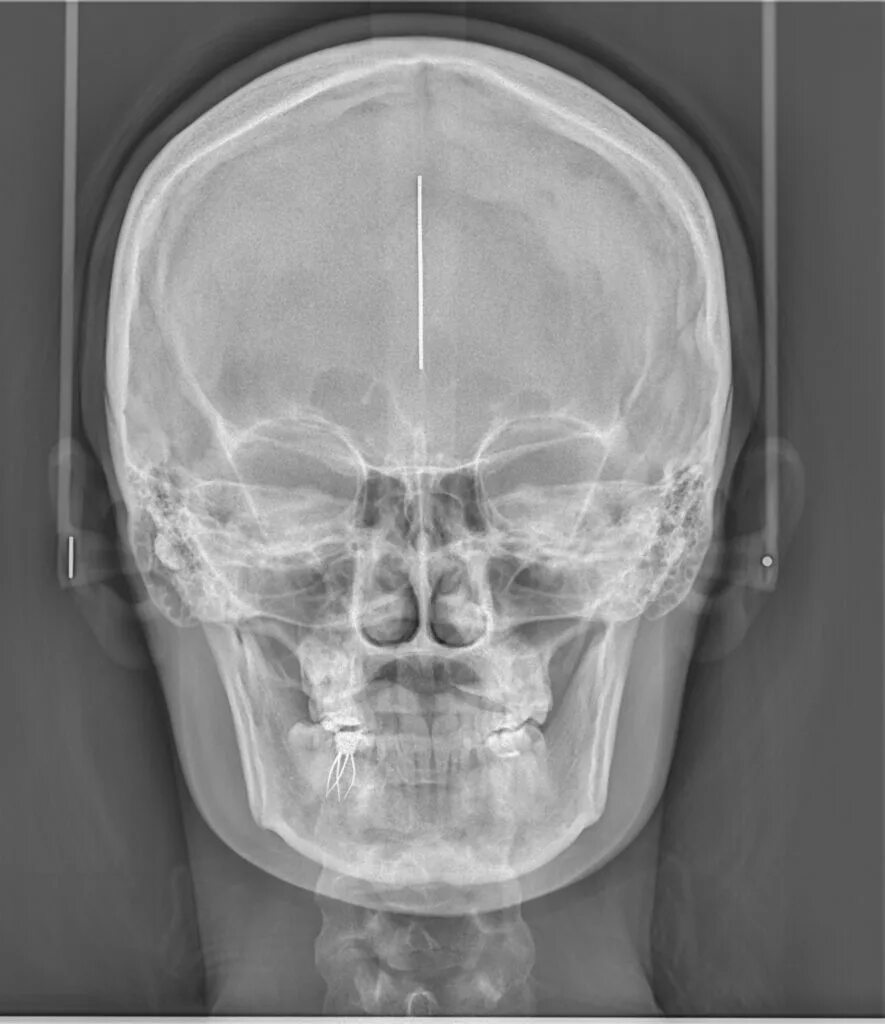

Снимок в прямой проекции